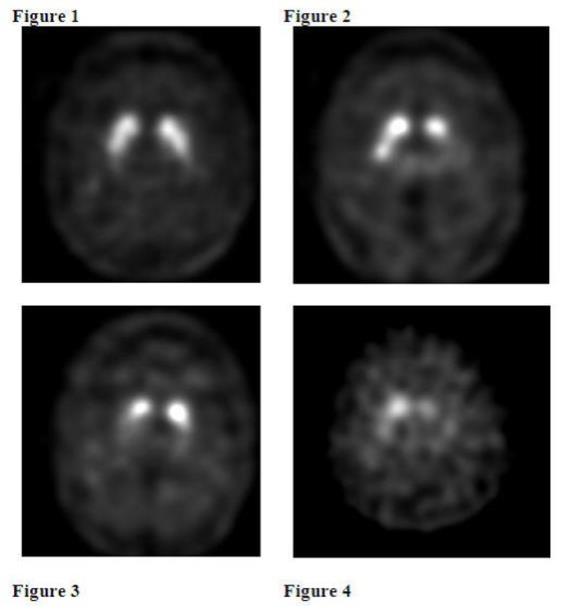

Interpret Ioflupane I 123 Injection images visually, based upon the appearance of the striata. Reconstructed pixel size should be between 3.5 mm and 4.5 mm with slices 1 pixel thick. Optimum presentation of the reconstructed images for visual interpretation is transaxial slices parallel to the anterior commissure-posterior commissure (AC-PC) line.

Determine whether an image is normal or abnormal by assessing the extent (as indicated by shape) and intensity of the striatal signal. Image interpretation does not involve integration of the striatal image appearance with clinical signs and/or symptoms.

Normal: In transaxial images, normal images are characterized by two symmetric comma- or crescent-shaped focal regions of activity mirrored about the median plane. Striatal activity is distinct, relative to surrounding brain tissue (Figure 1).

Abnormal: Abnormal Ioflupane I 123 Injection images fall into at least one of the following three categories (all are considered abnormal).

• Activity is asymmetric, e.g., activity in the region of the putamen of one hemisphere is absent or greatly reduced with respect to the other. Activity is still visible in the caudate nuclei of both hemispheres resulting in a comma or crescent shape in one and a circular or oval focus in the other. There may be reduced activity between at least one striatum and surrounding tissues (Figure 2).

• Activity is absent in the putamen of both hemispheres and confined to the caudate nuclei. Activity is relatively symmetric and forms two roughly circular or oval foci. Activity of one or both is generally reduced (Figure 3).

• Activity is absent in the putamen of both hemispheres and greatly reduced in one or both caudate nuclei. Activity of the striata with respect to the background is reduced (Figure 4).